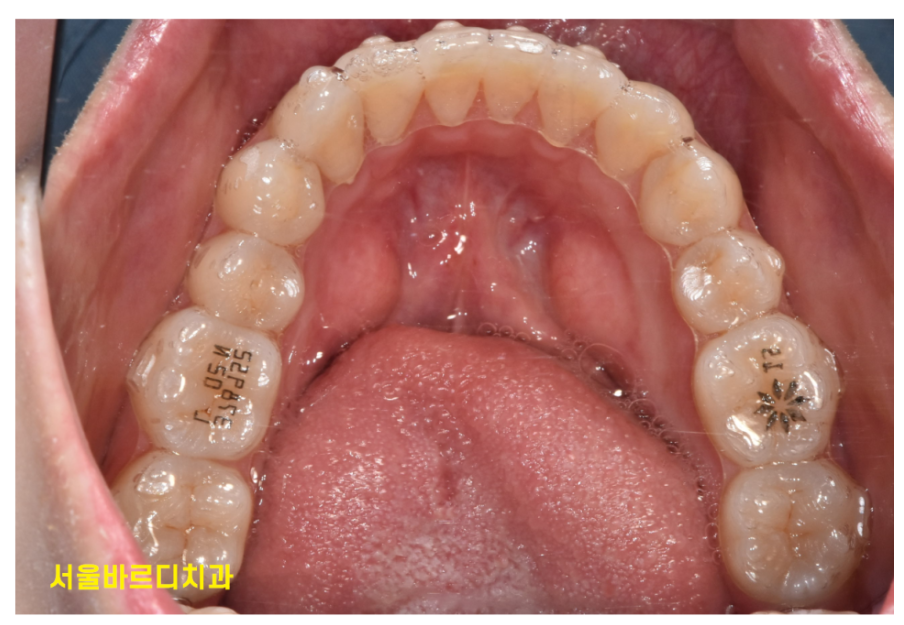

250328 치아가 벌어져 재교정을 결심하신 환자분

치아 사이가 벌어져 공간이 생겼거나